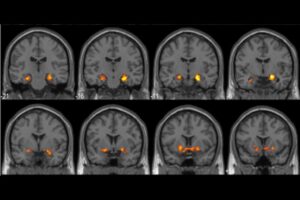

واستخدم فريق بحثي من جامعة ديوك وجامعة هومبولت، بقيادة البروفيسور روبرتو كابيزا، تقنية التصوير بالرنين المغناطيسي الوظيفي لرصد ما يحدث داخل الدماغ أثناء لحظات “الوجدان” أو “لحظة آها” (Aha moments)، وهي تعبير مجازي عن لحظة اكتشاف أو فهم فجائيه.

وعندما يمر الشخص بلحظة وجدان، يشهد الدماغ انفجارا حقيقيا في نشاط منطقة الحصين (قرن آمون)، تلك المنطقة الصغيرة التي تلعب دورا محوريا في عمليات التعلم وتكوين الذاكرة.

كما تظهر تغيرات جذرية في نمط إطلاق الخلايا العصبية في القشرة القذالية الصدغية البطنية، وهي المنطقة المسؤولة عن التعرف على الأنماط البصرية ومعالجة المعلومات المرئية.

ولعل الأكثر إثارة هو ما لاحظه العلماء من زيادة ملحوظة في كفاءة الاتصال بين مختلف مناطق الدماغ أثناء لحظات الإلهام. وكما يوضح البروفيسور كابيزا: “تتواصل المناطق المختلفة مع بعضها بعضا بشكل أكثر كفاءة أثناء هذه اللحظات”، ما يخلق نوعا من التكامل العصبي الفريد الذي يفسر قوة هذه التجارب وتأثيرها الدائم على الذاكرة.